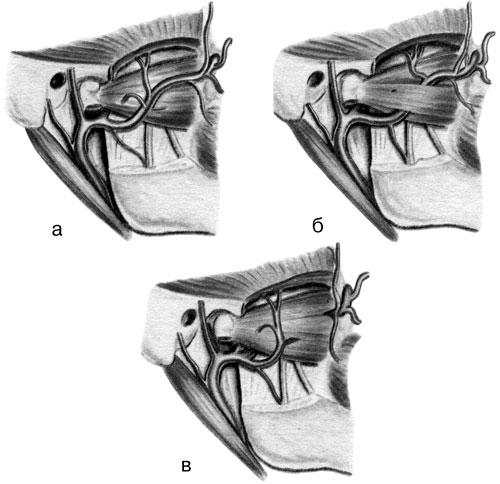

Угол оперативного действия может не только определяться параметрами костной раны, но и быть реверсивным при проникновении в полость (например, при трепанации верхнечелюстной пазухи) – рис. 19.

Рис. 19. Углы оперативного действия, образованные разными тканями: а – угол оперативного действия, ограниченный только мягкими тканями (при обширных дефектах мягких тканей); б – ограниченная величина угла оперативного действия, определяемая костными элементами (трепанация верхнечелюстной пазухи через ее переднюю стенку); в – реверсивный угол оперативного действия при проникновении в полость верхнечелюстной пазухи через лунку экстрагированного зуба (по: Мухин М. В., 1974).

• При величине угла оперативного действия более 90° для выполнения операции создаются идеальные условия.

• При величине угла от 26 до 89° выполнение манипуляций в ране не вызывает затруднений.

• При величине угла 25–15° оперативно-хирургические действия в ране затруднены.

• При величине угла менее 15° манипуляции в ране невозможны.